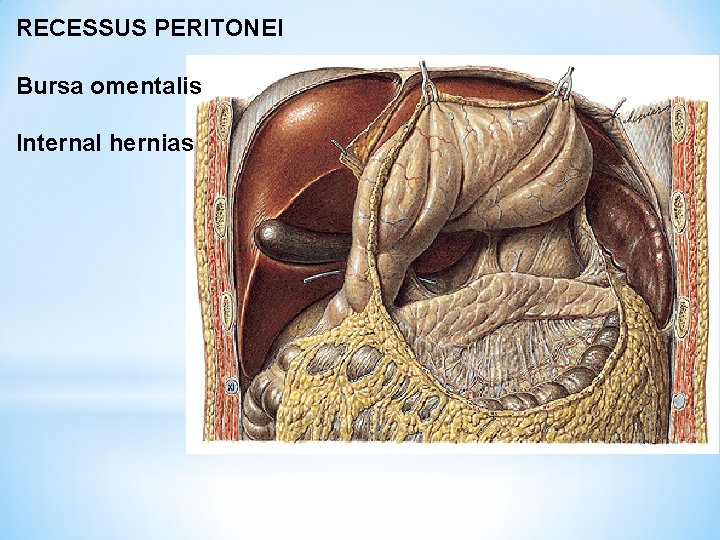

RECESSUS PERITONEI Bursa omentalis Internal hernias

Bursa omentalis

Foramen omentale/epiploicum (Winslow) Recessus sup. , splenicus, inf.

Recessus inferior bursae omentalis